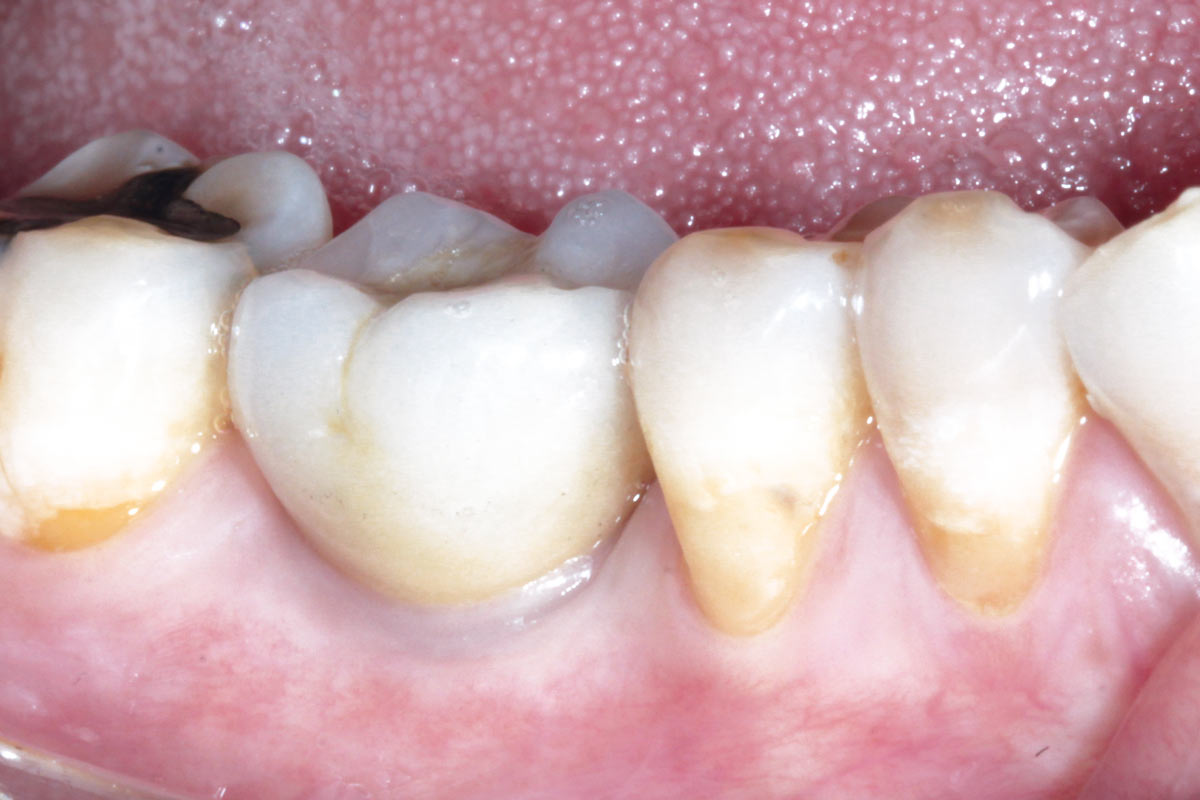

13/19 - Healing 3 month post-op

Immediate implant placement using maxresorb® - Dr. Alejandro Signorio

14/19 - Healing 3 month post-op